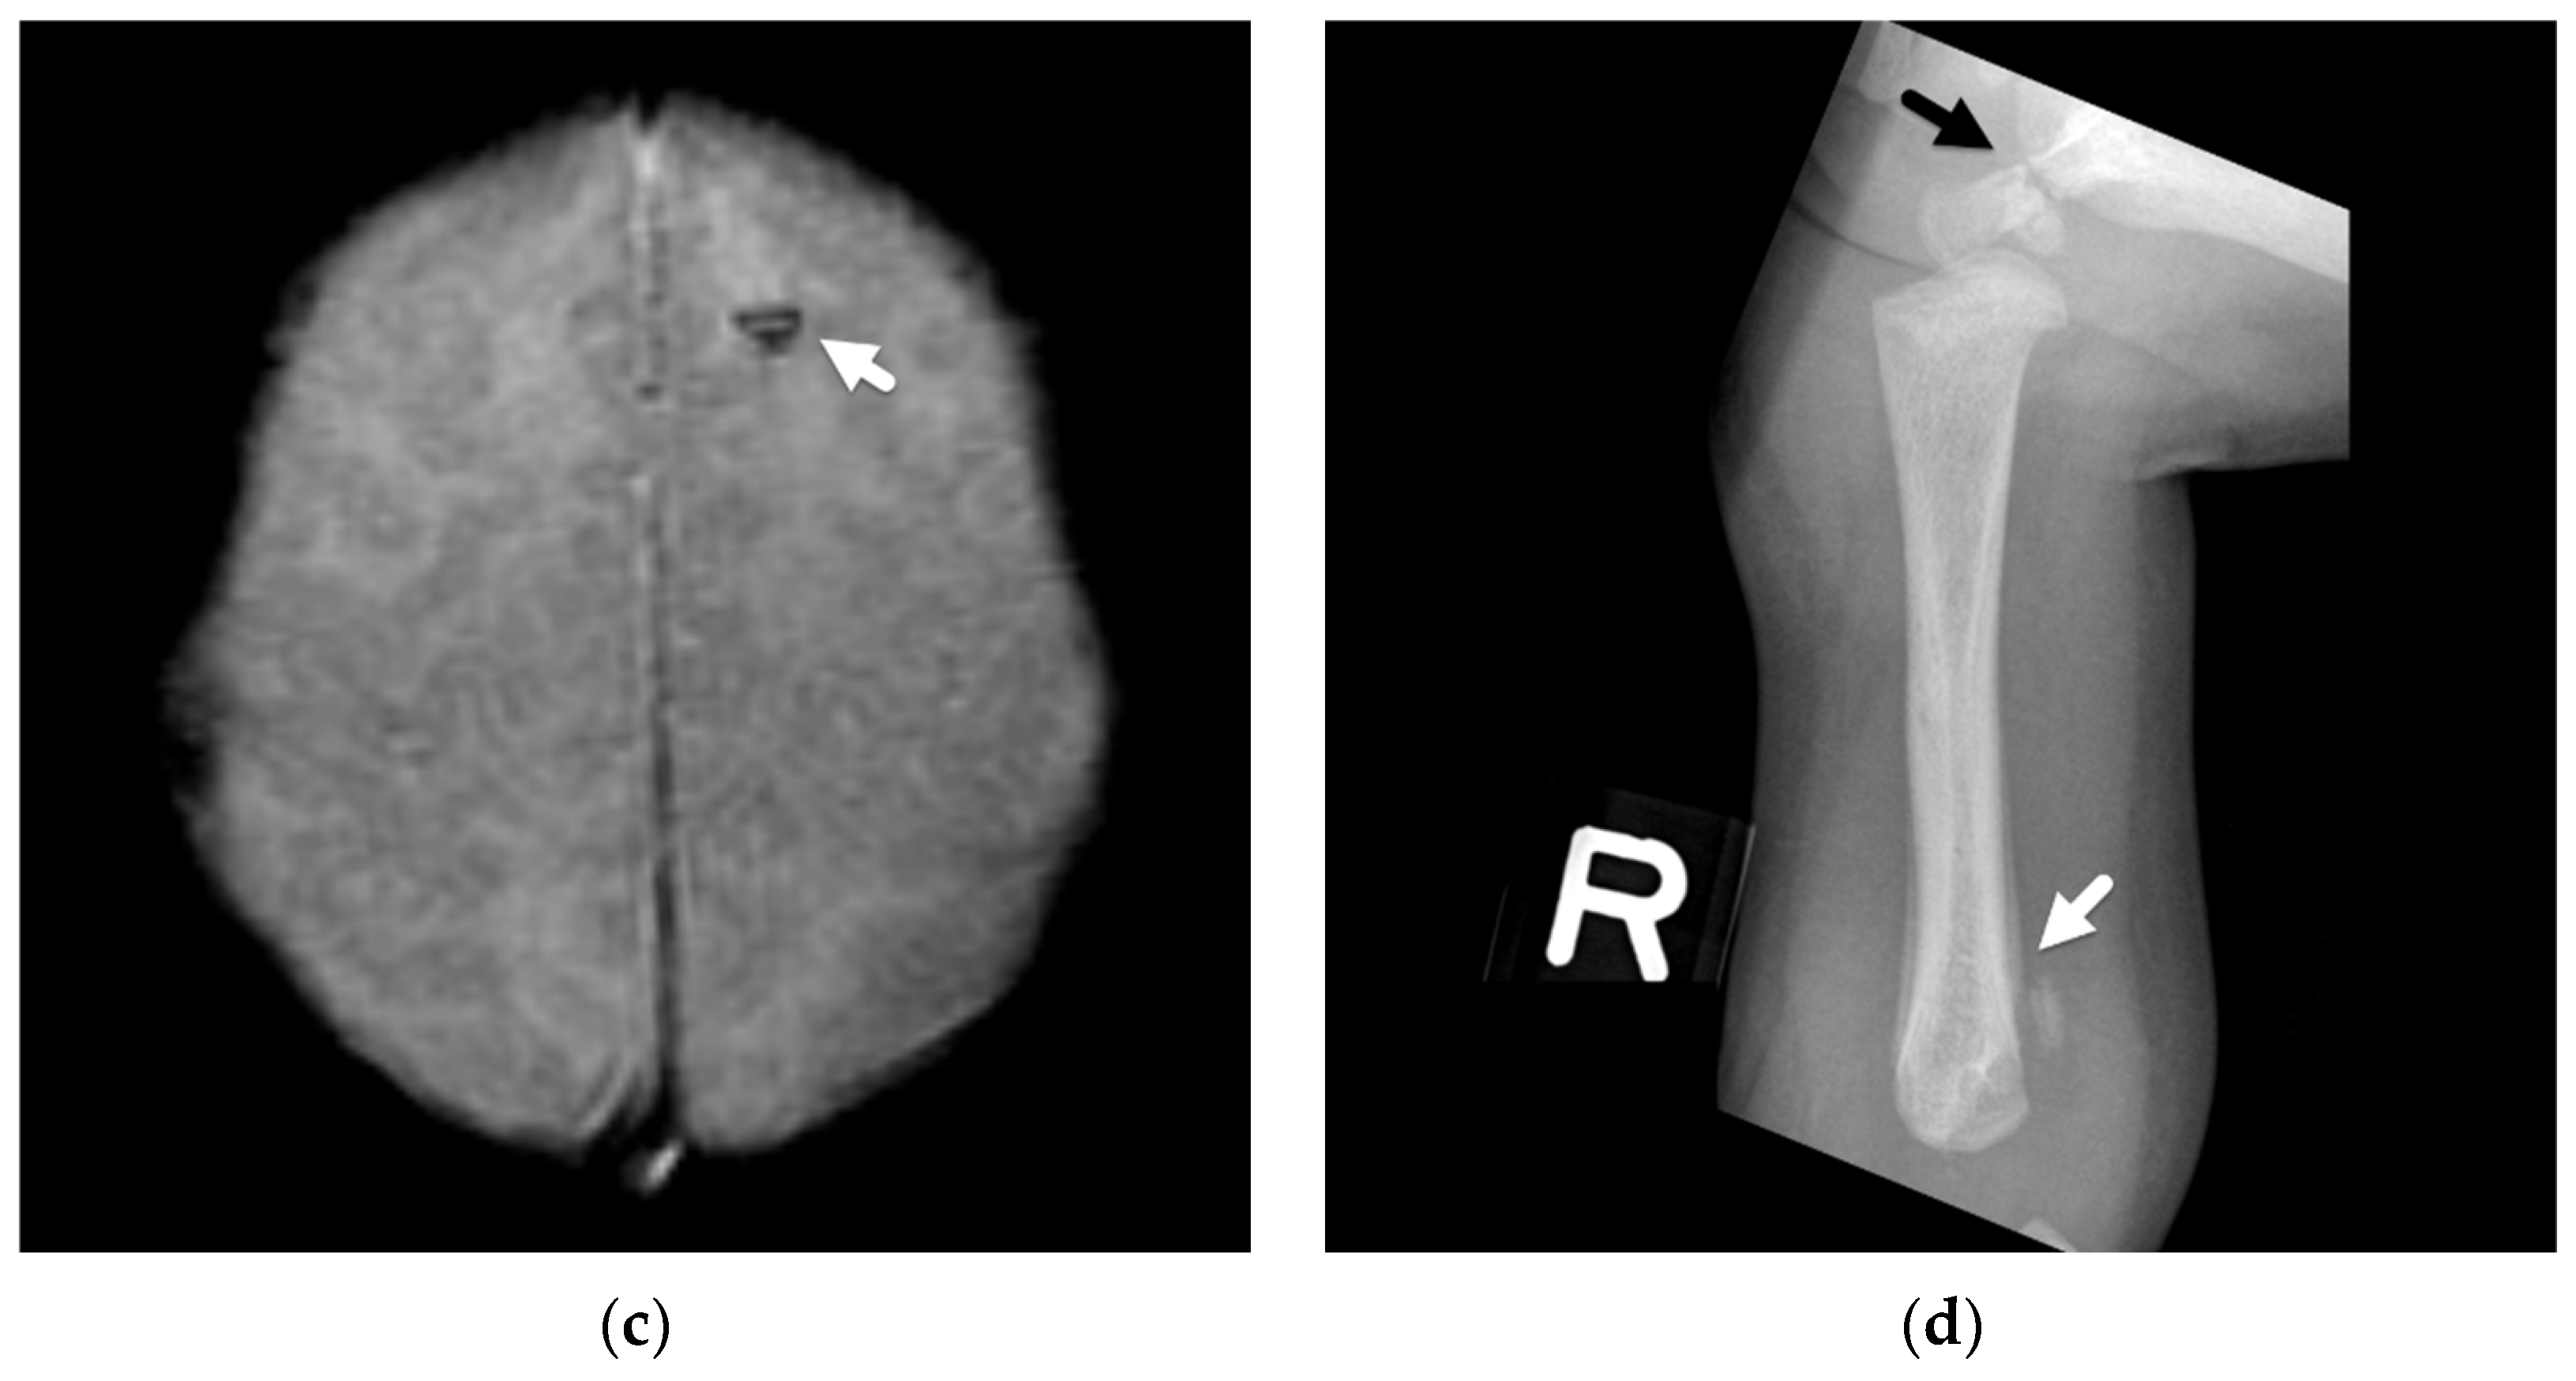

Traumatic head injury may also result directly in parenchymal contusions and lacerations. These injuries are also less commonly observed in abusive head trauma [24,25,26,28] but, when present, are frequently seen in conjunction with other traumatic injuries, such as overlying extra-axial hemorrhage or fractures (Figure 5). Given their more focal nature, these insults typically result in more localized neurologic deficits instead of a diffuse encephalopathy, although they certainly can be seen in conjunction with more diffuse injuries. In Zimmerman et al.’s review of DWI in abusive head trauma [25], parenchymal contusions were one of the least frequent patterns of described parenchymal injury, occurring in only 2/33 cases, potentially reflecting different mechanisms of injury in the abusive head injury population as opposed to a direct cranial insult from an accident, such as when a child accidentally falls from a second-story window. Other studies have also demonstrated the more infrequent occurrence of contusions in this population [24,27]. Contusions more commonly affect older children, are often multiple, maybe hemorrhagic or non-hemorrhagic, and are usually centered near the surface of the frontal and temporal lobes near the adjacent bone surfaces and dural reflections. Multiplanar CT reconstructions will allow increased detection of subtle contusions in the inferior frontal and anterior temporal lobes. On MRI, gradient echo or susceptibility-weighted imaging will aid in detection of more subtle hemorrhagic contusions, while non-hemorrhagic contusions may be more readily detected on diffusion-weighted imaging along the surface of the brain. Contusions often increase in size over the first few days as well as develop surrounding edema.

Figure 5.

Skull fracture and hemorrhagic contusion in a 2-month-old female presenting with the history of a fall off a couch. (a) Initial axial CT demonstrates a hemorrhagic contusion at the posterior temporal-parietal lobe junction (white arrow) with mixed but predominantly low-attenuation hemorrhagic subdural (black arrow). More focal loss of gray-white matter differentiation (black arrowhead) may also suggest coexistent venous infarction or bland contusion; (b) coronal CT reconstruction shows the hemorrhagic contusion (white arrow) deep to a diastatic right parietal bone fracture (white arrowhead); (c) three-dimensional reconstruction of the skull demonstrates a mildly complex right parietal bones fracture (black arrows) and right frontal bone fracture (white arrow).